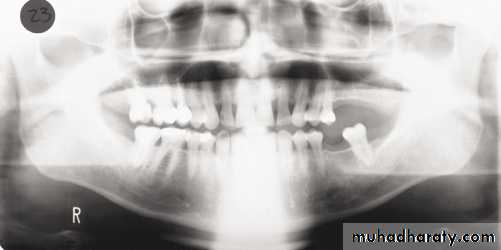

Patient too far back; note ghosting of mandible and spine, condyles pushed to outside of film, blurring and widening of anterior teeth